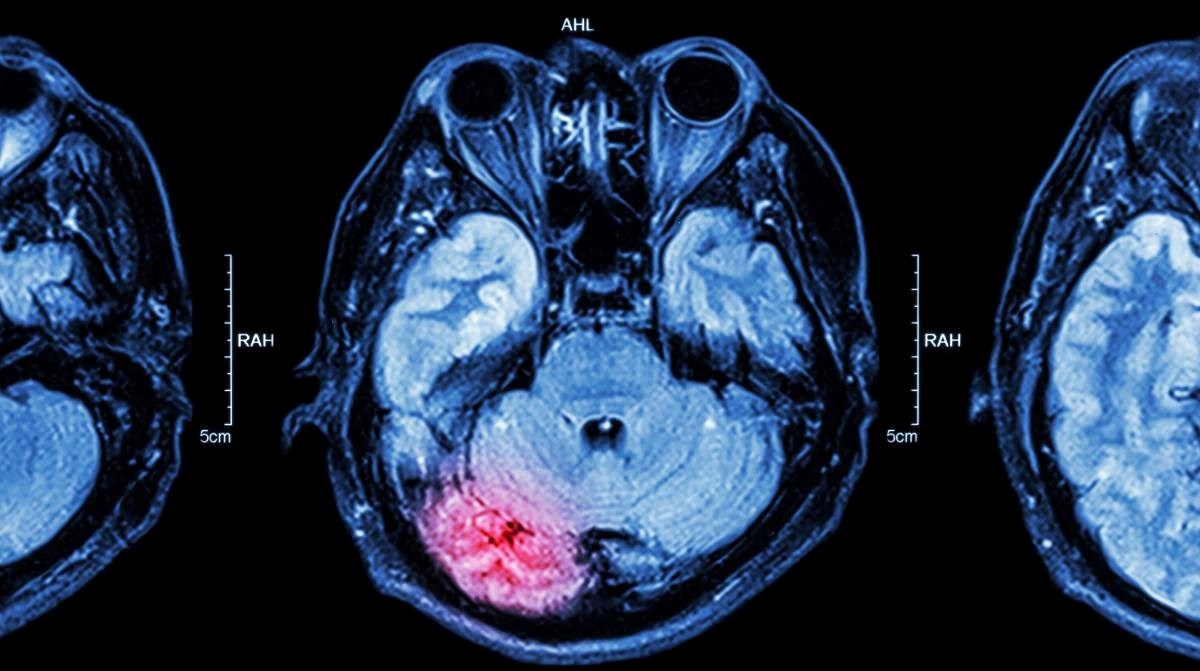

JAPANSKI znanstvenik razvio je tehniku koja pomoću AI i snimki mozga pretvara vizualne misli u tekst. Tehnologija ima potencijal za medicinsku primjenu, ali pokreće i ozbiljna etička pitanja.